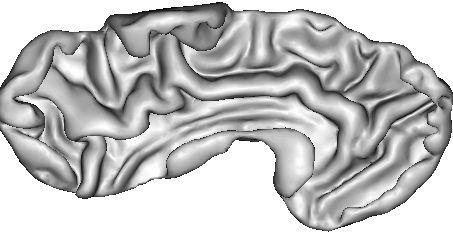

The resulting grey/white interface can be converted into a mesh endowed with the spherical topology, which will be inflated by some other Brainvisa treatments for visualization purpose (Ana Inflate Cortical Surface):

A dilation of this interface towards the outer brain edges may lead to nice 3D rendering of the cortical surface, which are easy to read because the folds are opened (Ana Get Opened Hemi Surface) :